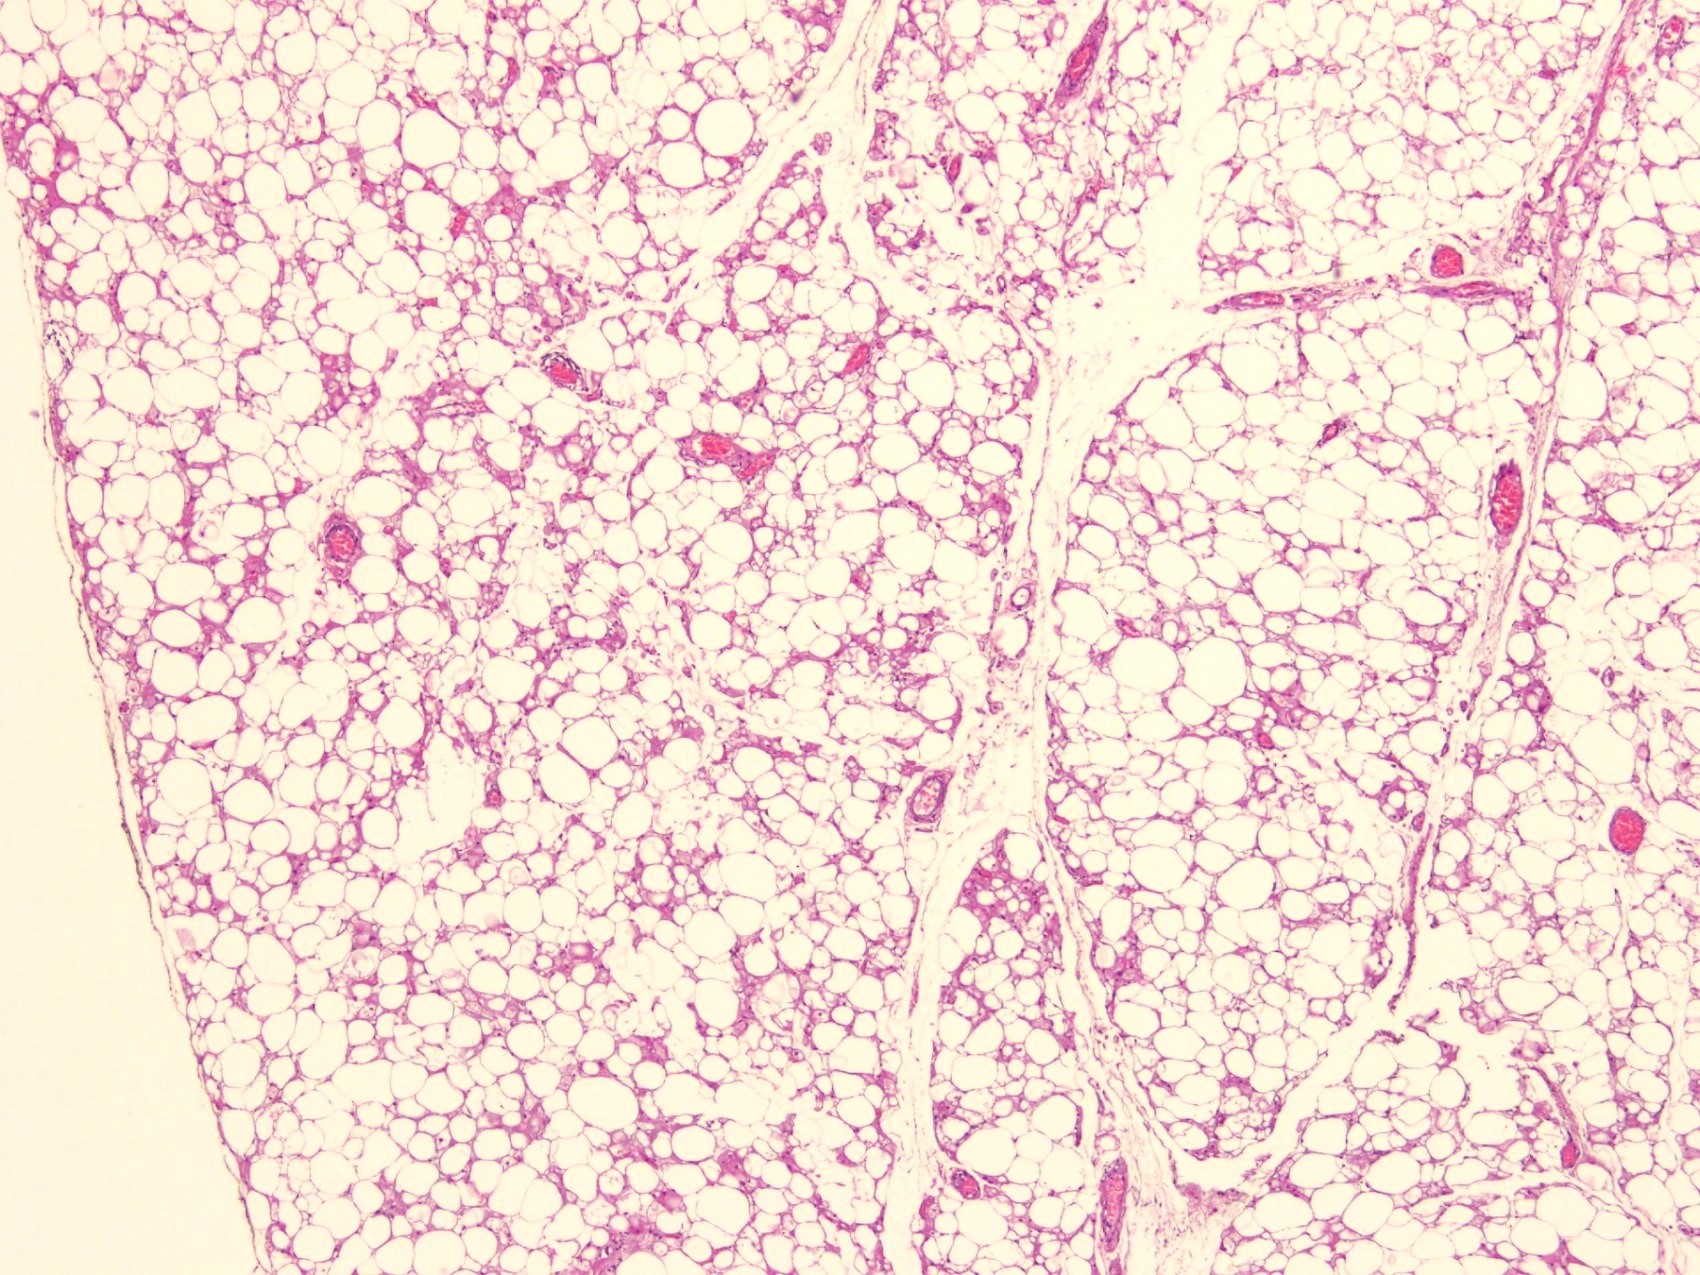

Microscopic (histologic) description

- Neoplastic lesion composed of polygonal brown fat cells with stromal cells in the background (Case Rep Oncol 2017;10:438)

- Large number of pale and eosinophilic brown fat cells with multivacuolated, eosinophilic granular cytoplasm and small central nucleus (about 70%) admixed with variable amount of univacuolated white cells (Case Rep Oncol 2017;10:438, Am J Case Rep 2020;21:e921447, J Comput Assist Tomogr 2019;43:793, J Pathol Transl Med 2017;51:499, Am J Surg Pathol 2018;42:951, Virchows Arch 2021;478:527)

- Multivacuolations resemble lipoblasts

- Morphological variations or subtypes: typical, myxoid (9%), lipoma-like (7%), spindle cell (2%), thick bundles of collagen fibers, presence of mast cells and exclusively containing brown fat cells (Case Rep Oncol 2017;10:438, Am J Case Rep 2020;21:e921447, Virchows Arch 2021;478:527)

- Cytological atypia, necrosis and mitosis is unusual (J Pathol Transl Med 2017;51:499, Am J Surg Pathol 2018;42:951, BMC Surg 2021;21:30)

Microscopic (histologic) images